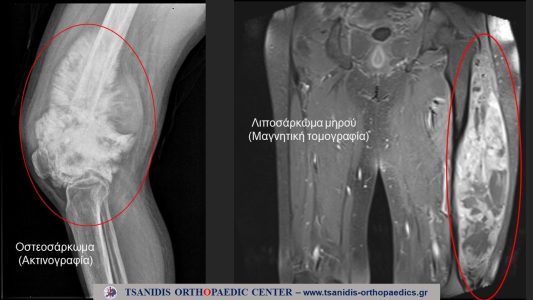

Οι όγκοι αυτοί εμφανίζονται στα άκρα, χέρια και στα πόδια, στο κοιλιακό τοίχωμα, στη ράχη και στη λεκάνη. Οι όγκοι αυτοί μπορεί να είναι καλοήθεις ή κακοήθεις (σαρκώματα). Πιο συχνοί τέτοιοι όγκοι είναι το λίπωμα, το λιποσάρκωμα, το οστεοσάρκωμα, ο γιγαντοκυτταρικός όγκος, η ανευρυσματική κύστη, το οστεοειδές οστέωμα, το ίνωμα, το σάρκωμα Ewing, το εγχόνδρωμα, το χονδροσάρκωμα, το συνοβιακό σάρκωμα, το ίνωμα, το χόρδωμα, η εξόστωση, το οστεοβλάστωμα και αρκετοί άλλοι.

Απαιτείται, εξειδικευμένη σε τέτοιους όγκους, διαγνωστική ομάδα με συντονιστή τον εξειδικευμένο ορθοπαιδικό χειρουργό σαρκωμάτων. Ο απεικονιστικός έλεγχος περιλαμβάνει ψηφιακές ακτινογραφίες, υπερηχογράφημα, μαγνητική τομογραφία (MRI). Διενέργεια αξονικών τομογραφιών (CT) και σπινθηρογραφήματος οστών για την σταδιοποίηση του όγκου. Η διάγνωση ολοκληρώνεται με βιοψία από την πάσχουσα περιοχή. Η βιοψία διενεργείται συνήθως με βελόνη υπό καθοδήγηση με αξονικό τομογράφο ή από υπερηχογράφο. Οι «ανοιχτές» (με τομή) βιοψίες δεν συνιστώνται. Ελπίδες για ευκολότερη διάγνωση αφήνει η νέα τεχνική της «υγρής βιοψίας» (Liquid biopsy) και στηρίζεται τις μεταλλάξεις του DNA.